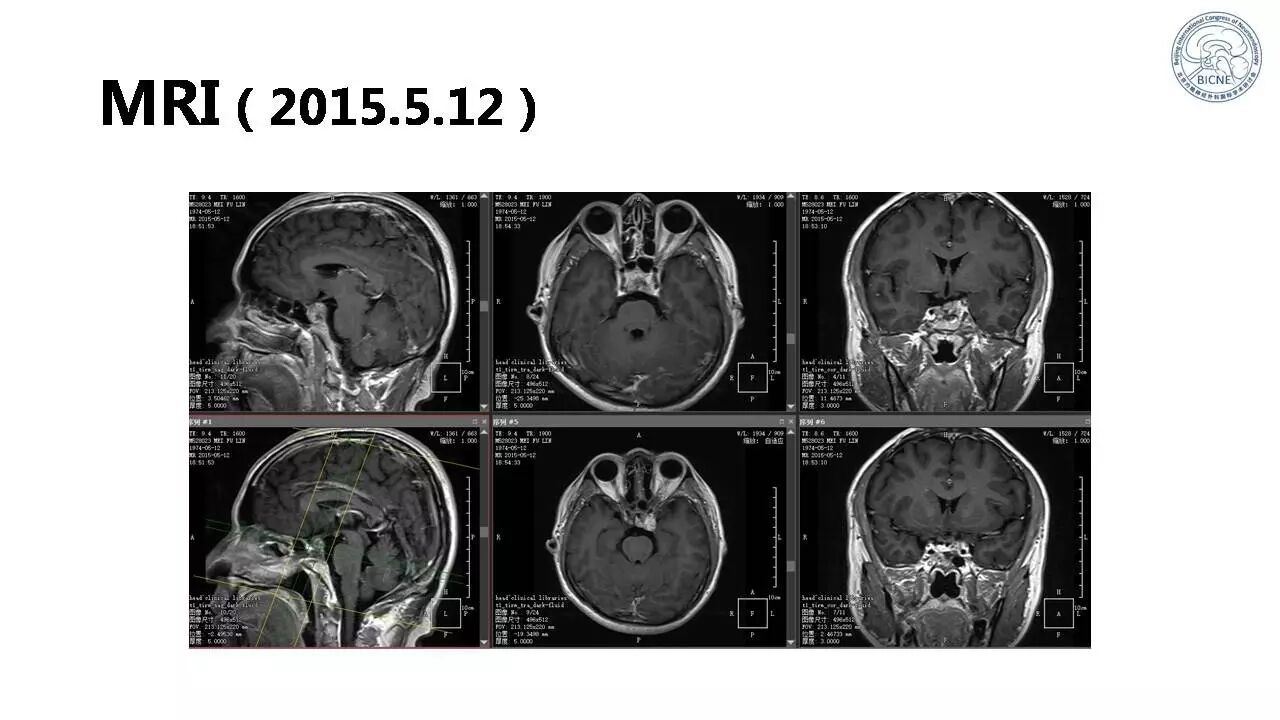

(一)张亚卓教授:脊索瘤经鼻内镜下治疗

![]()